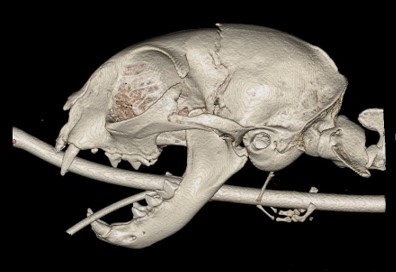

- Le scanner